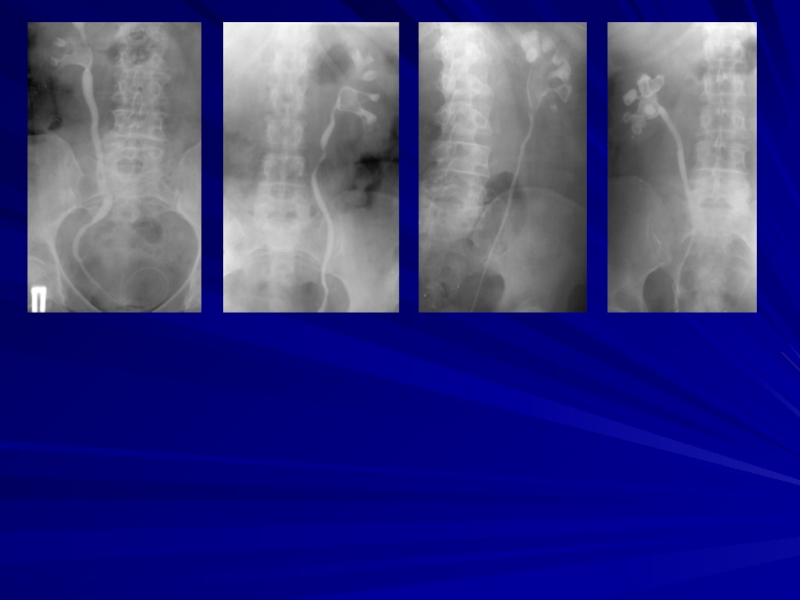

Слайд 34Дистанционная литотрипсия

под R-контролем

Дистанционная литотрипсия

под УЗ-контролем